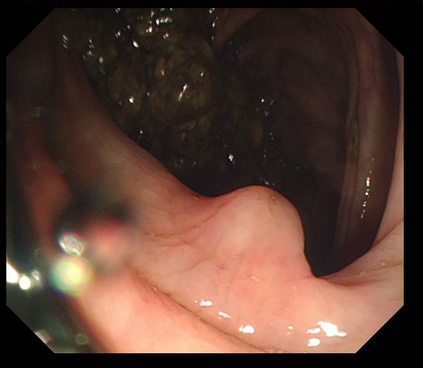

Polyps are early cancer indicators, so assessing occurrences of polyps and their removal is critical. They are observed through a colonoscopy screening procedure that generates a stream of video frames. Segmenting polyps in their natural video screening procedure has several challenges, such as the co-existence of imaging artefacts, motion blur, and floating debris. Most existing polyp segmentation algorithms are developed on curated still image datasets that do not represent real-world colonoscopy. Their performance often degrades on video data. We propose a video polyp segmentation method that performs self-supervised learning as an auxiliary task and a spatial-temporal self-attention mechanism for improved representation learning. Our end-to-end configuration and joint optimisation of losses enable the network to learn more discriminative contextual features in videos. Our experimental results demonstrate an improvement with respect to several state-of-the-art (SOTA) methods. Our ablation study also confirms that the choice of the proposed joint end-to-end training improves network accuracy by over 3% and nearly 10% on both the Dice similarity coefficient and intersection-over-union compared to the recently proposed method PNS+ and Polyp-PVT, respectively. Results on previously unseen video data indicate that the proposed method generalises.